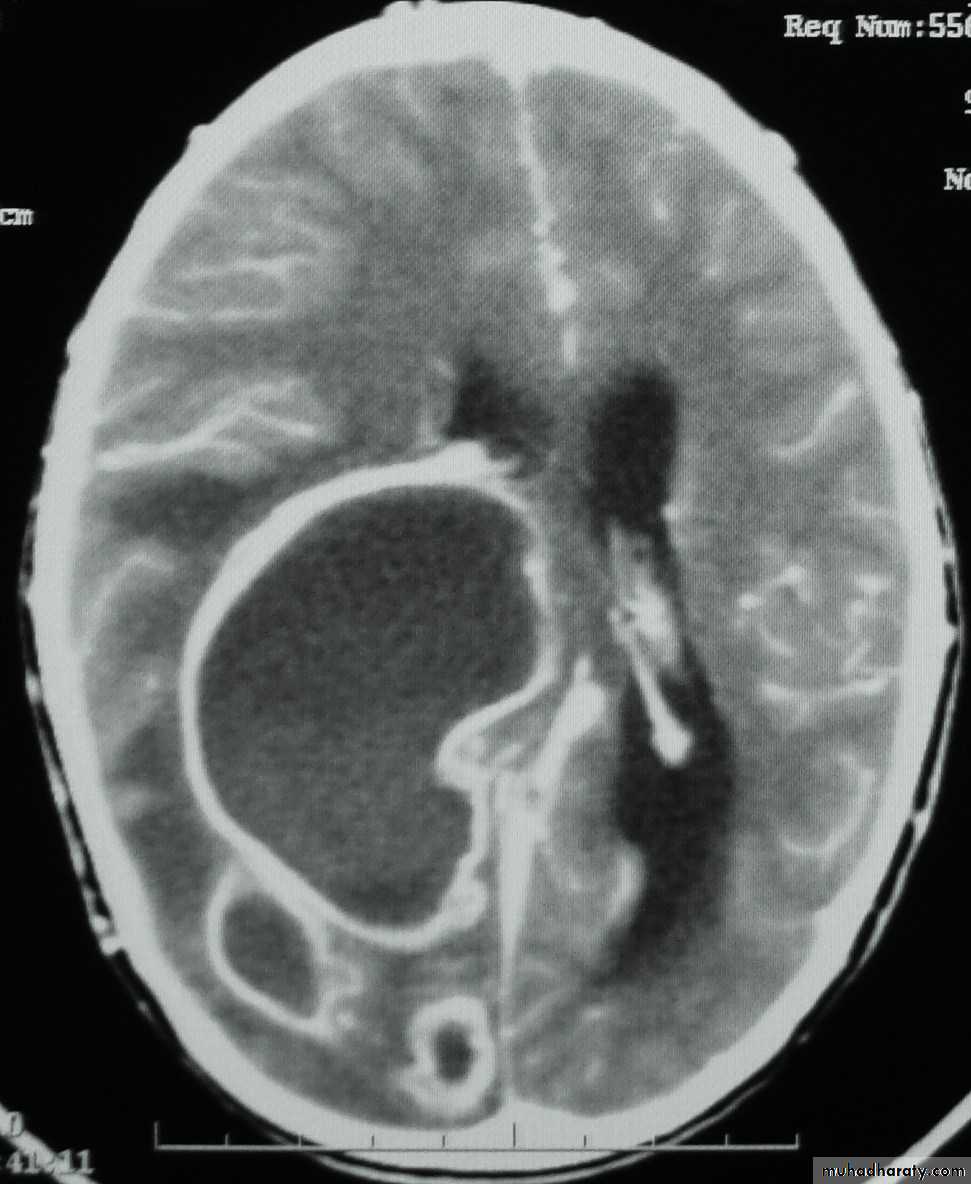

Cerebellar Abscess

د.عبدالرحمن

• Indications for Excision (Craniotomy):

• Multilocular abscess.

• A superficial abscess.

• The presence of a foreign body.

• Fungal abscess.

• Cerebellar Abscesses.

• Abscesses containing air.

• Abscesses with CSF leak.

• Abscess which fail to resolve.